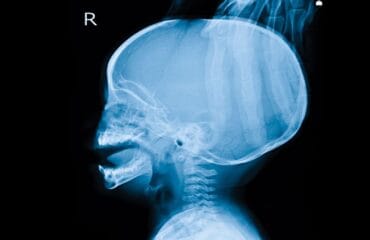

Tumor spinal adalah perkembangan sel tidak normal pada area sekitar tulang belakang. Kondisi ini bisa bersifat ganas atau kanker atau bersifat jinak. Tumor bisa menyebar ke bagian tubuh lainnya apabila penanganan terlambat. Anda dapat memeriksakan diri ke dokter apabila mengalami gejala tumor.

Tumor spinal adalah kondisi ketika tubuh mengalami perkembangan sel abnormal yang berada di dalam atau luar sekitar sumsum dan tulang belakang. Kondisi ini bisa bersifat jinak (non-kanker) atau tumor ganas (bersifat kanker).

Jika tumor terus berkembang, tubuh dapat mengalami kerusakan pada berbagai jaringan di tulang belakang. Berdasarkan lokasinya, kondisi ini terbagi atas beberapa jenis, antara lain: